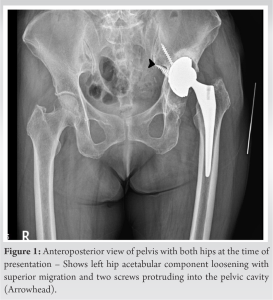

A 64-year-old female patient complaining of progressive shortening of the left lower limb for the past 1 year was admitted to our hospital. She was operated for left THA 3 years ago in some other hospital. The clinical examination of the left hip showed restricted flexion range, abduction range, and external rotation of the hip with a true shortening of 3 cm. Surgical scars from previous surgery had healed well. There was no fever, local warmth, local redness, or tenderness present. A plain anteroposterior radiograph of the pelvis with both hips showed acetabular component loosening and superior migration. Screws used for acetabular shell fixation were found to be protruding into the pelvis, medial to Kohler’s line (Ilioischial line) in the unsafe zone (Fig. 1).